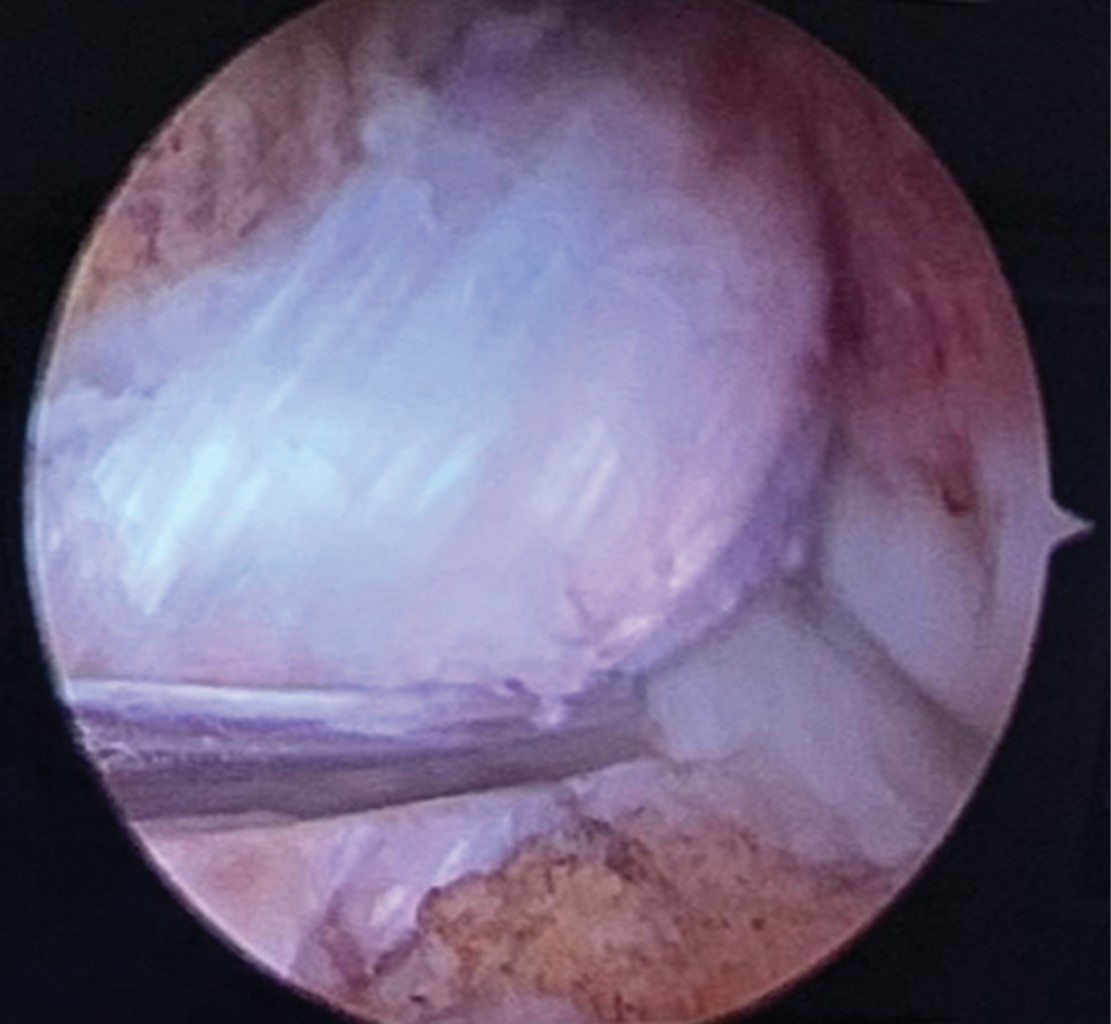

Anteromedial. Previa realización de túneles y selección de tamaño de Endobutton se pasa clavo guía por túnel femoral con una sutura de vycril del 0 o 00 para posteriormente recuperarla por el túnel tibial. Ya con la sutura se pasa el injerto con el sistema Endobutton (Figuras 1 y 2).

Transtibial. Es el mismo procedimiento que en el abordaje anteromedial, pero todo se realiza a través del tunel tibial.

Figura 1

Figura 2